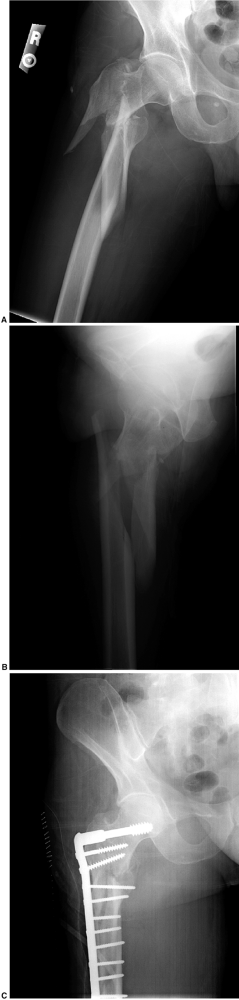

wide, threaded, blunt-nosed screw offers the best mechanical fixation

for intertrochanteric fractures (Fig. 23-1). With unstable fracture patterns, a trochanteric plate may be used to prevent excessive collapse (31). -

Figure 23-1.

A sliding screw plate. Note the proper positioning for maximum fixation

with the screw centrally seated in the head within 1 cm of the

subchondral bone. Four screws are used to insert the slide plate onto

the femur.

Figure 23-2. Reverse obliquity fracture.